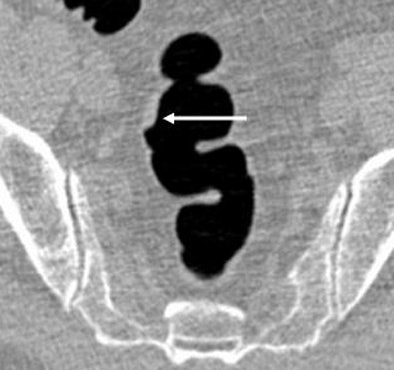

| Three views of a flat lesion: 60-year-old man with an 11-mm tubular adenoma seen at 2D (top) and 3D (below) VC, but initially missed at endoscopy (bottom). All images courtesy of Dr. Michael Macari. |

Segmental unblinded colonoscopy showed a total of six patients with seven polyps 10 mm or larger, including pedunculated (n = 1), sessile (n = 2), and flat (n = 4). Sensitivity was 43% (3/7) for VC with tagging, 86% (6/7) for VC with full bowel prep and 71% (5/7) for first-pass optical colonoscopy, the authors reported.

Three of four lesions missed with tagging had flat morphology. There were no significant differences (p > 0.12) among the three modalities with respect to sensitivity for detecting polyps 10 mm or larger.

"In the tagged lesions, three of the four missed lesions (at VC) were, in fact, flat," Macari said. The remaining flat lesion went undetected in 2D VC, "but during 3D review I noticed this flat lesion and it was confirmed at (optical colonoscopy)," he said. "So that means 3D is really helpful."